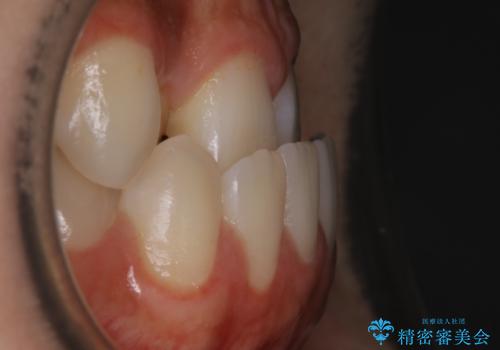

本来、正常な噛み合わせの場合は上顎の前歯が下顎の前歯より前に覆いかぶさるように噛み込んでくる状態が理想的です。

それに対して「反対咬合(受け口)」の場合は、下顎の前歯が上顎の前歯より前に出てきてしまう状態を指します。

その原因は ①骨格的問題 ②機能的問題 の2つに大きく分かれます。

①に関しては外科的手術を併用した矯正治療を必要とする場合が多く、大学病院や専門の設備を備えた医院での治療が必要となります。

原因が②であった場合は、手術を必要とせず口腔内ではの位置を変えてあげるだけで噛み合わせや顔貌を変化させることができる場合があります。